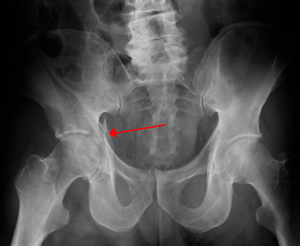

Acetabular fracture as seen on plain X-ray | |

Fractures of the acetabulum occur when the head of the femur is driven into the pelvis. This is caused either by a blow on the side or by a blow in the front of the knee, usually in a dashboard injury when the femur also may be fractured.[1]

To understand fracture pattern it is essential to have minimum three x-ray views;

- · Pelvis with both hips antero posterior view

This view shows six important landmarks of the acetabulum, viz;

- 1. Pelvic brim

- 2. Ilio ischial line

- 3. Tear drop

- 4. Anterior wall

- 5. Posterior wall

- 6. Weight bearing dome